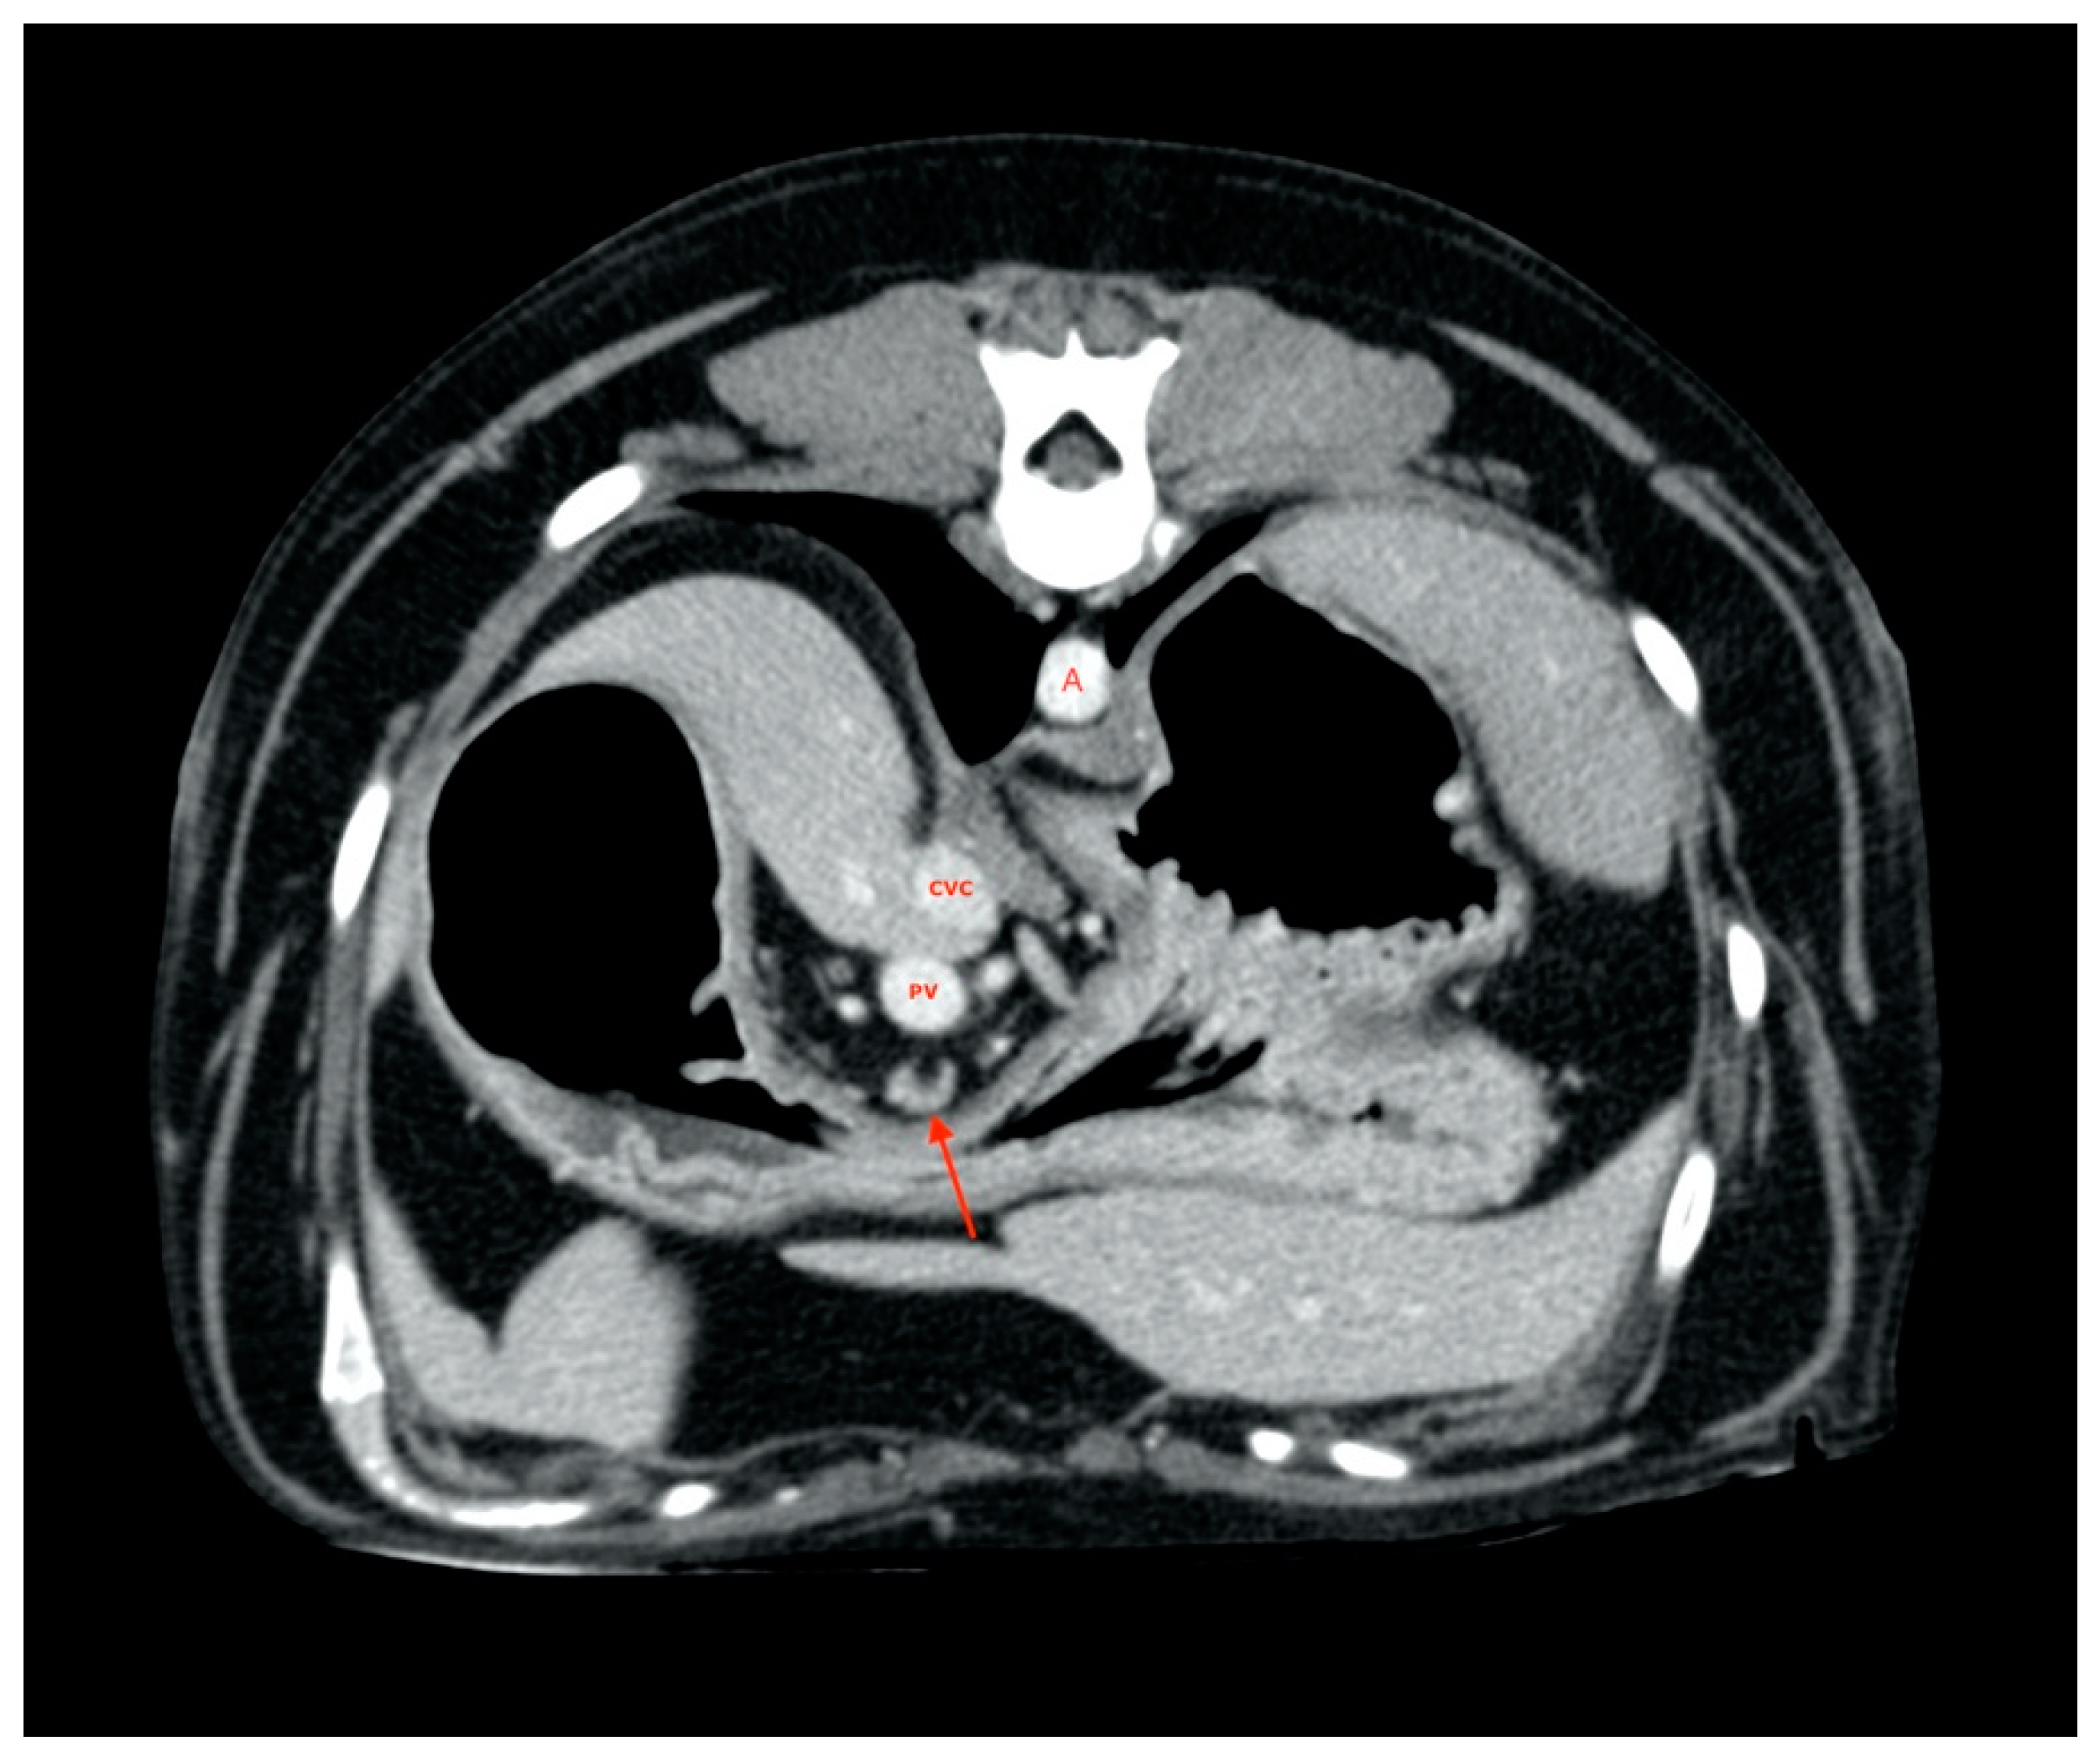

2.4. Procedures

2.5. Measurements